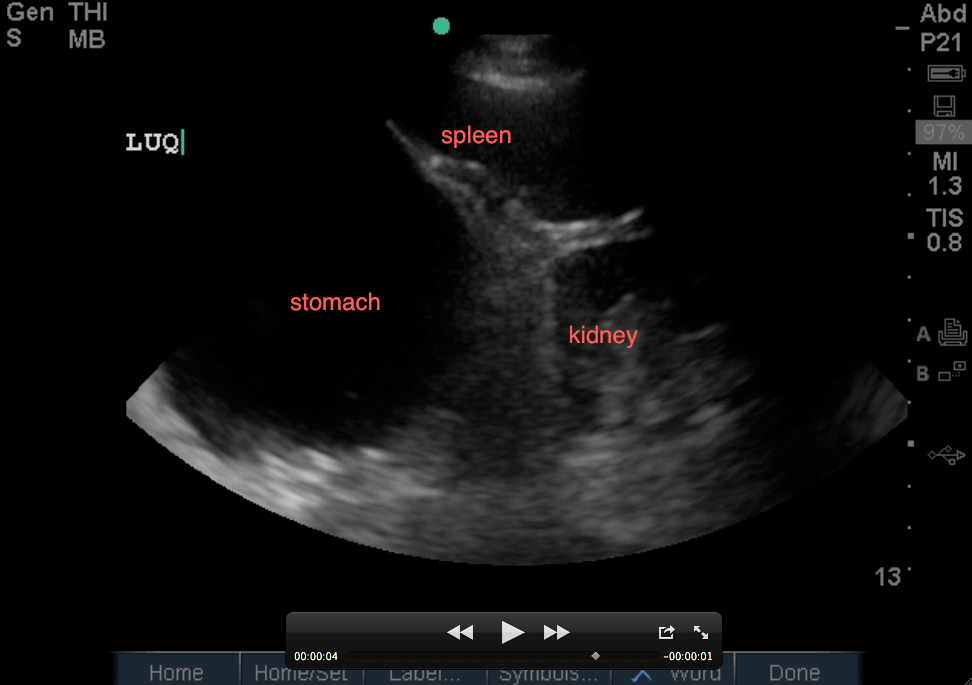

Let’s get into the LUQ view: First, assess that your probe is in the correct location by seeing (from top of screen to bottom): the spleen on your screen and slowly angling it posteriorly to get the kidney also on your screen which is right above the psoas and then spine (with it’s shadow). If you do not see the spleen, you may be too high or too low – slide down or up a rib space to get yourself oriented to the correct region with the depth usually being at 13-16cm using your phased-array low frequency probe.